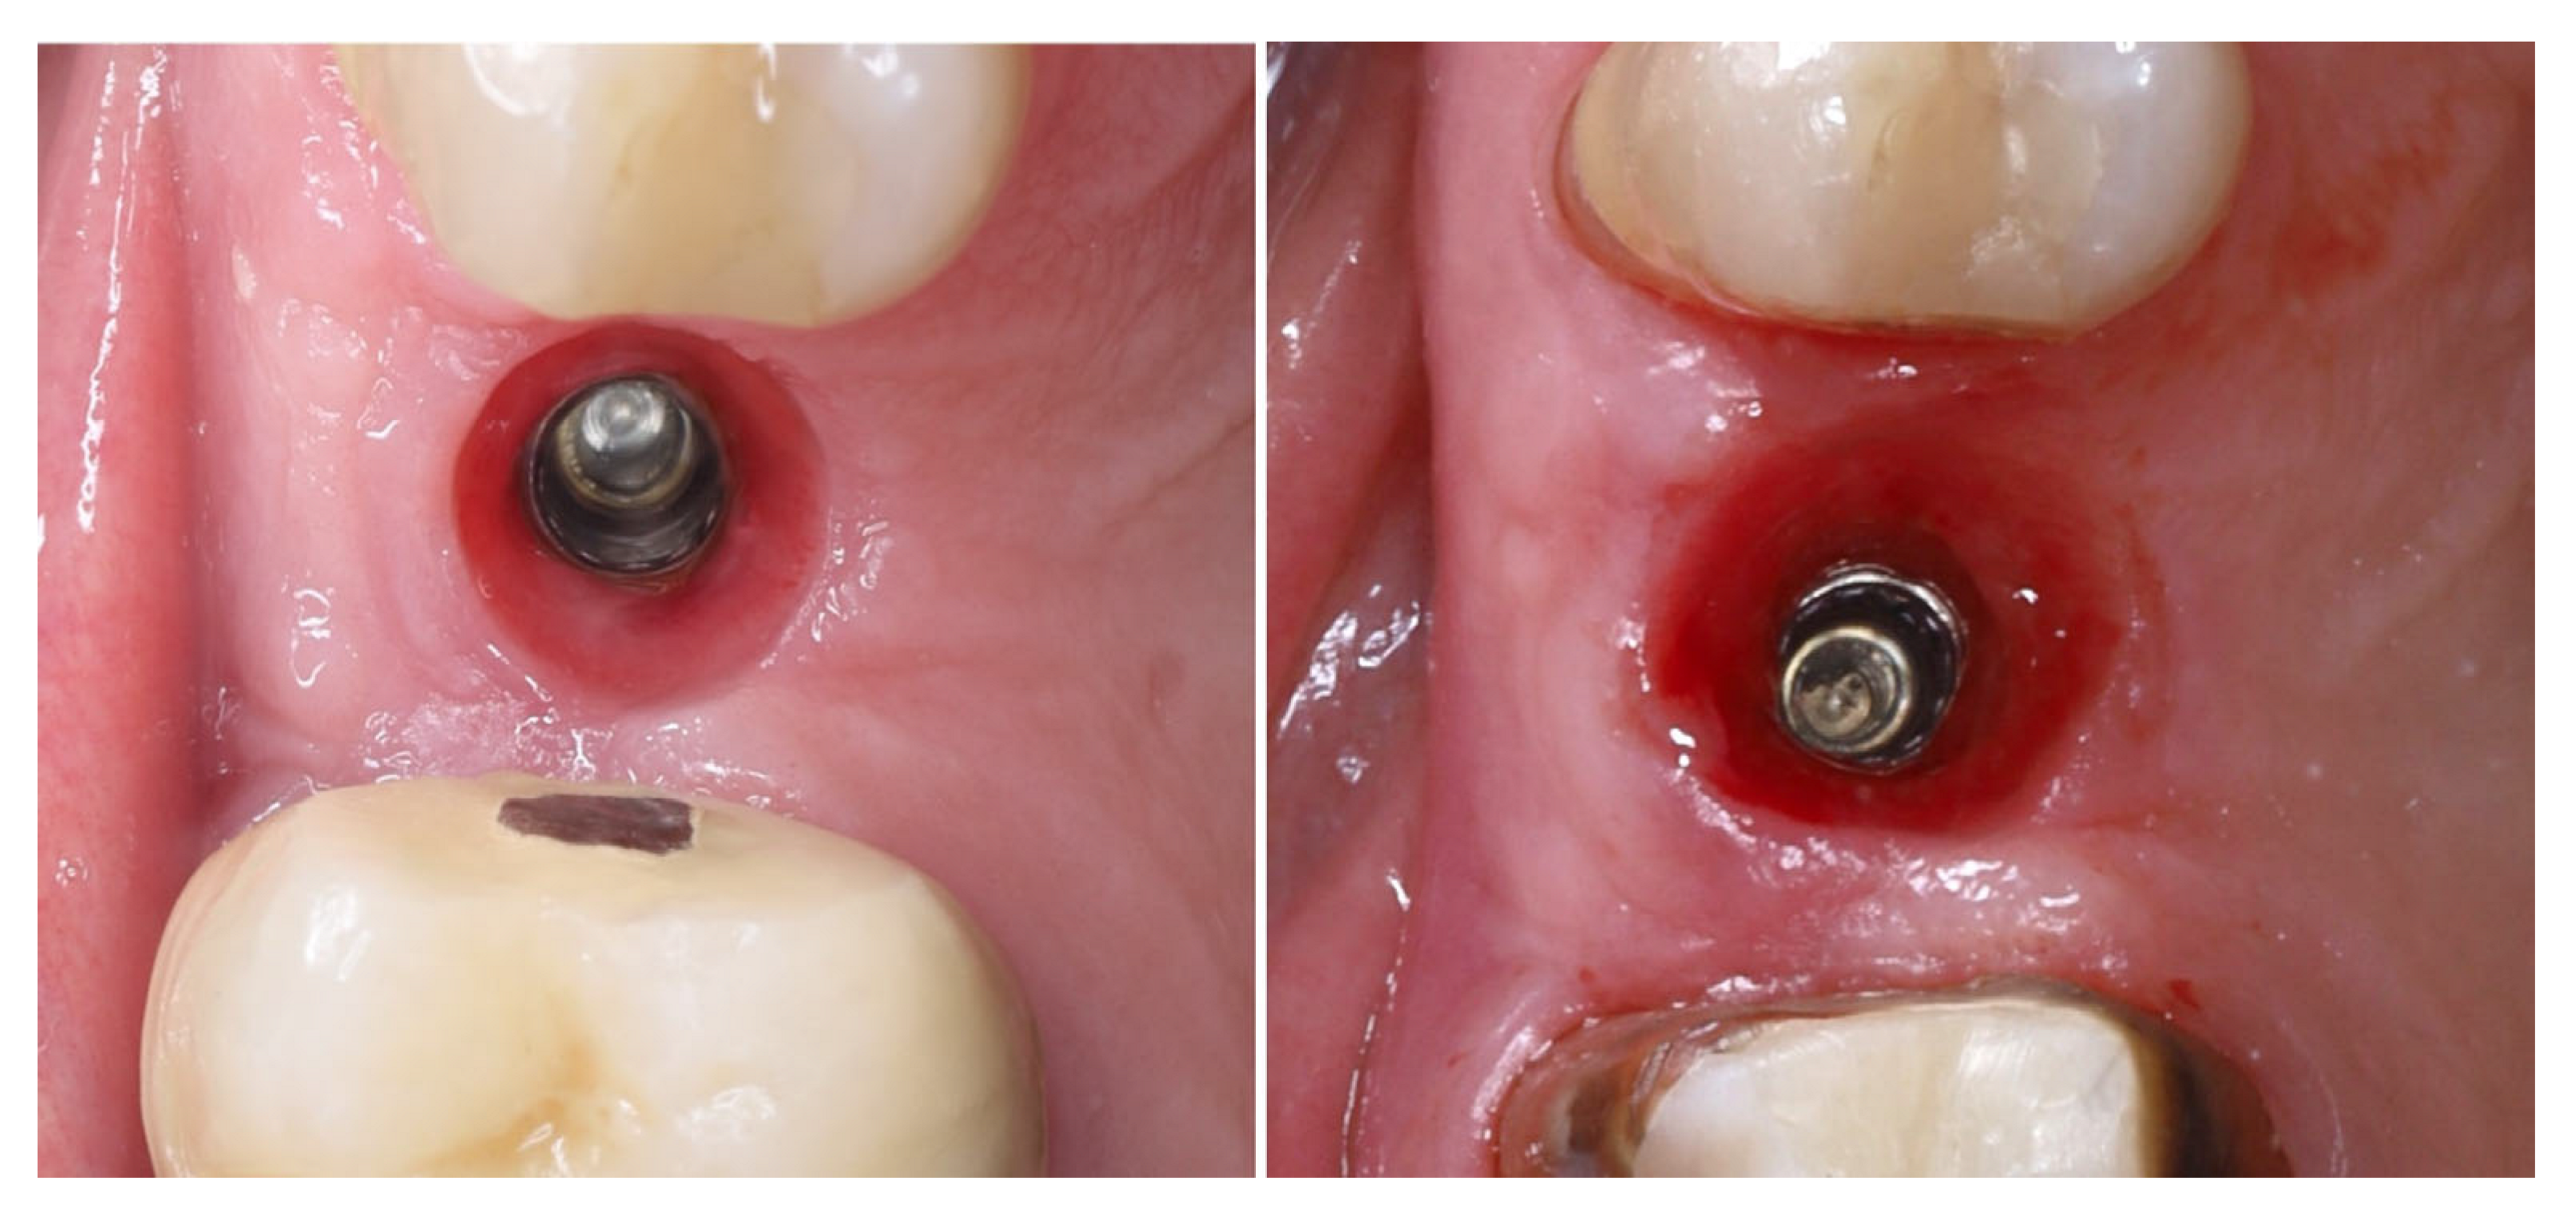

| Timepoint | Horizontal Thickness (mm) | Vertical Thickness (mm) | Clinical/Radiographic Findings | |

|---|---|---|---|---|

| 1 | Baseline (Day 0) | 2.3 | 2.4 | Initial thin buccal tissue |

| 2 | 2 weeks post-op | Uneventful healing, stable mucosal margin | ||

| 3 | 3 months post-op (with provisional) | 3.4 | 3.4 | Increased thickness, stable bone and mucosa |

| 4 | 4 months post-provisional | 3.5 | 3.6 | Stable peri-implant mucosa around provisional crown |

| 5 | 8 months post-op (final crown) | 3.5 | 4.1 | Final crown placed, harmonious soft tissue contours, and stable crestal bone |

| 6 | 14 months post-definitive | Long-term stability of soft tissue and crestal bone confirmed |